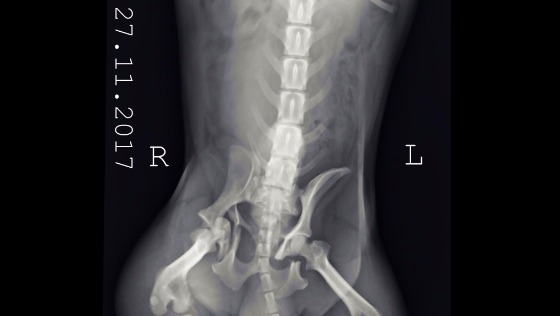

Po konsultacjach z weterynarzem konieczna jest operacja rekonstrukcji obustronnie połamanej miednicy i kości. Zmiażdżona jest też panewka stawu biodrowego. Połamane kości utrudniają wypróżnianie bo uciskają na jelita psa,. Nerwy nie są na szczęście uszkodzone. Nie może chodzić. Konieczne są środki przeciwbólowe.

Koszt samej operacji oszacowano wstępnie na 3000zł. Dziś kolejne konsultacje. Konieczne są implanty. Dotychczasowe wizyty u weterynarza w związku z całą tą sytuacją już pochłonęły znaczne środki z naszego budżetu.